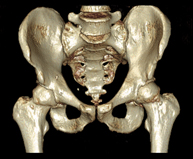

- TC Pelvis ósea

Exploración radiológica que mediante un sistema de rayos X y detectores que giran alrededor del paciente, reconstruyendo las imágenes por ordenador (TC Multidetector), permite el estudio de huesos, músculos y articulaciones de la pelvis.

- TC Caderas

Exploración radiológica que mediante un sistema de rayos X y detectores que giran alrededor del paciente, reconstruyendo las imágenes por ordenador (TC Multidetector), permite el estudio de huesos, músculos y articulaciones de la cadera.